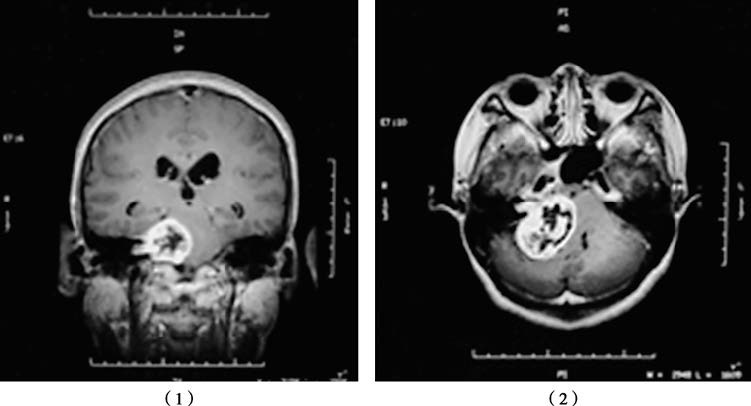

Figure 1 MRI scans of a right-sided vestibular schwannoma in coronal (1) and axial (2) views, showing a round lesion in the internal auditory canal.

Thin-slice axial MRI scans often identify a round or oval-shaped contrast-enhancing mass in the internal auditory canal, with larger tumors potentially showing cystic degeneration. CT scans may reveal an expanded internal auditory canal with a funnel-shaped appearance and associated bone erosion.